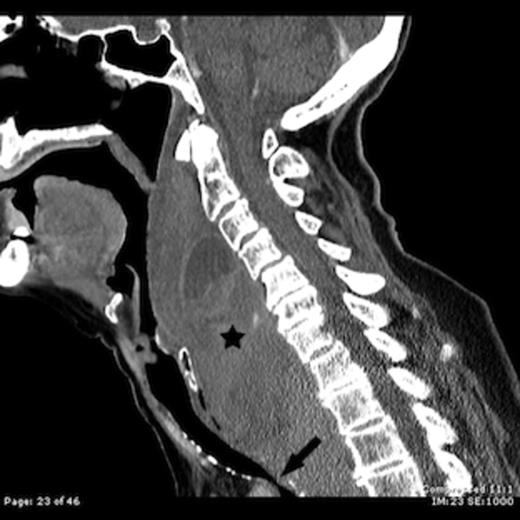

Contrast enhanced sagittal CT image shows a large retropharyngeal haematoma (star) extending from the C2 vertebral level to below the level of the sternal notch with tracheal compression (arrow)

Computed tomography (CT) of the brain, neck and chest was performed. A massive retropharyngeal haematoma was observed extending between C2 and T4 vertebral body levels with displacement and compression of the trachea (Figure 1,2). There was no evidence of carotid, vertebral or internal jugular vein injury and no cervical fracture.